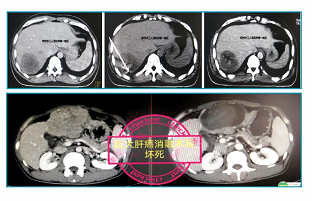

肝脏肿瘤介入载药微球栓塞、消融后肿瘤明显坏死